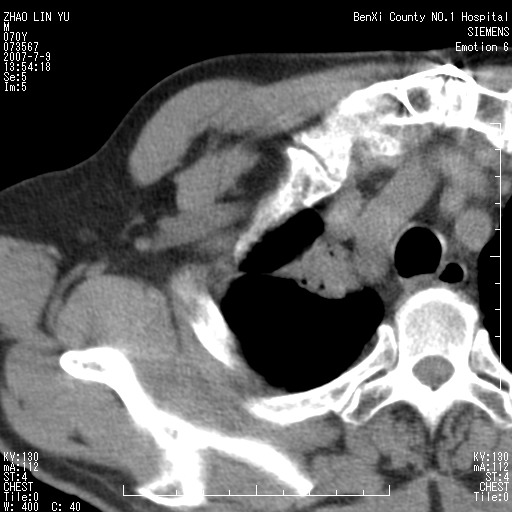

以下是引用王靖旗在2007-7-10 17:12:00的发言:[br] 男、70、咳嗽两个月,半年前换瓣手术,胸片未见异常,于昨天行x片发现右肺上野大片影,行ct扫描,这里是减薄图像,余肺正常。明天晚上会有增强扫描片,到时我会上传。[br][br] 冠状位请大家细看,应该是有意义的,[br][br] 请大家先看平扫发表意见。[br][br]

以下是引用zhangzhongshou在2007-7-10 21:43:00的发言:[br]右肺上叶周围型肺癌,以孤立型细支气管肺泡癌可能性大。